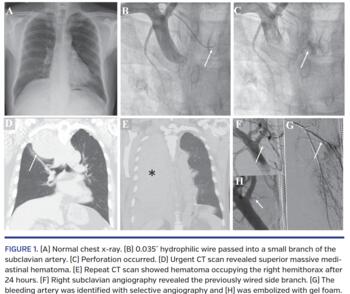

A 64-year-old man with hypertension presented with chest pain 1 month prior to admission. Electrocardiogram showed ST-segment depression in precordial leads. Chest radiography was unremarkable (Figure 1A). Right transradial coronary angiography was performed and percutaneous coronary intervention (PCI) was planned for the left anterior descending artery and right coronary artery. A hydrophilic wire glided transiently into a branch of the right subclavian artery during passage of the guiding catheter (Figure 1B; Video 1). The patient complained of mild back pain and subclavian artery angiography demonstrated a perforation, as shown by contrast extravasation (Figure 1C; Video 2). Protamine was intravenously administered to reverse heparin (Video 3). Repeat angiography showed no effusion 30 minutes later. An urgent computed tomography (CT) scan revealed superior massive mediastinal hematoma (Figure 1D). Repeated blood tests demonstrated a decreased hemoglobin from preprocedure value of 130 g/L to 68 g/L at 24 hours post procedure, and he was stabilized with fluid challenge and transfusion. Repeat CT scan demonstrated a high-density collection of the right hemithorax (Figure 1E; Video 4). This bleed was successfully treated by gel-foam embolization of the feeder artery after the trachea was intubated (Figures 1F, 1G, and 1H; Video 5). Two weeks after the procedure, he underwent surgical removal of the chest hematoma. Six weeks later, the left anterior descending and right coronary artery were successfully stented and he was discharged uneventfully.

This is the first reported case with evidence of the hydrophilic wire into a small branch and induced perforation; it highlights the need for fluoroscopically guided hydrophilic wire manipulation. Prompt treatment of such perforations is the best option.